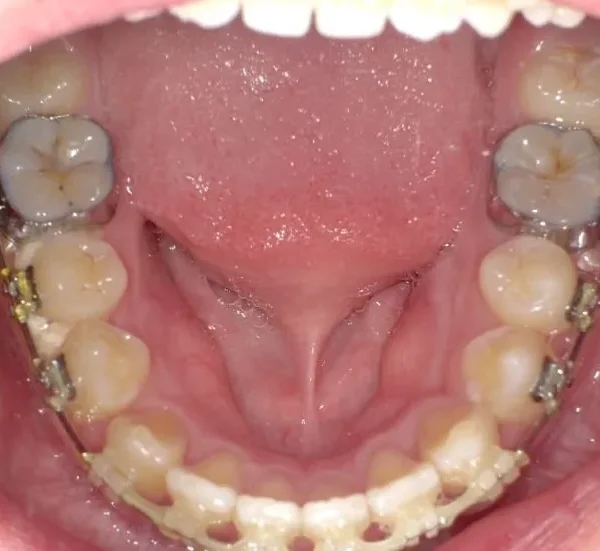

• 治療経過1

治療経過1